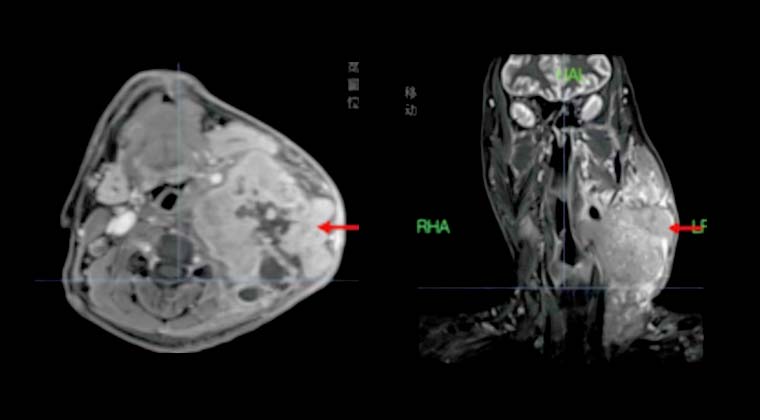

② Случай 2:

Пациент: Мужчина, 47 лет

Диагноз: Злокачественная опухоль носоглотки (дифференцированная неороговевающая карцинома носоглотки, cT4N3M1, стадия IV)

Симптомы: Периодическое головокружение, сухость во рту, жажда, полиурия

30.12022 - проведена радиотерапия TOMO

Дозы облучения: PGTV 69,96 Гр / 2,12 Гр / 33 фракции, PTVn 66 Гр / 33 фракции, PTV 60 Гр / 33 фракции

Через 3 месяца после лечения при визуализации отмечалось значительное уменьшение размеров и числа множественных метастазов в шейных лимфоузлах.

До лечения:

После лечения: